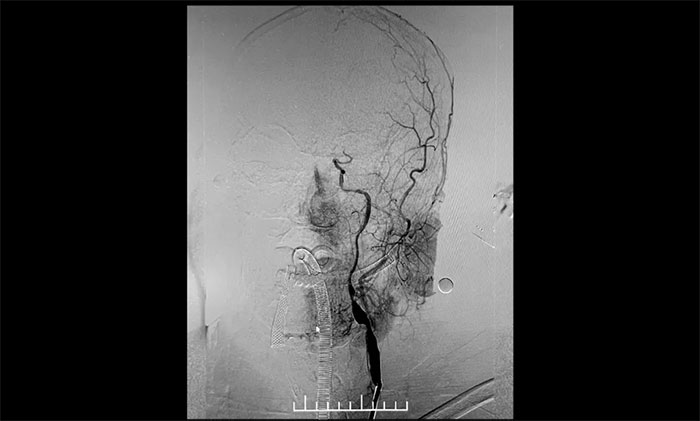

▲ 左颈内动脉起始段重度狭窄,并串联多处狭窄、闭塞

患者为老年男性,因言语不利,伴右侧肢体活动不利入院。外院行头颅CT检查:双侧脑室旁及基底节区腔隙灶。入院后,头颅MRI平扫+DWI+MRA提示,脑干、双侧小脑及双侧大脑半球多发腔梗、缺血灶;MRA:脑动脉硬化,左侧颈内动脉不完全闭塞,右侧颈内动脉C3-C6段、右侧大脑中动脉M2段多发狭窄。“主动脉弓+全脑动脉造影”提示:右颈内动脉起始段重度狭窄,左颈内动脉起始段重度狭窄,串联左颈内动脉岩骨段中度狭窄,左颈内动脉眼动脉段闭塞。

双侧颈内动脉起始段狭窄90%,并且左侧颈动脉属于串联病变。根据患者临床症状及造影结果,席刚明教授、王贵平博士考虑患者双侧大脑半球血流明显灌注不足,属于卒中高危病人,如不开通颈内动脉,反复脑梗死风险极高。但是,如果同时处理两侧颈动脉发生高灌注综合症风险高。